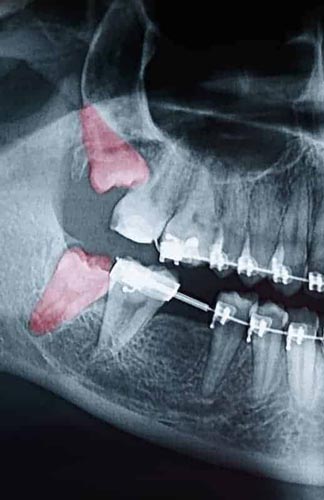

Though some patients may not require the removal of their wisdom teeth, most often, it’s needed to protect your overall oral health. Wisdom teeth can begin to grow sideways, only partially erupt, or even get stuck beneath the gum and bone. Known as impacted teeth, those that get stuck may resort to shifting positions as they try to find a pathway for eruption. When wisdom teeth don’t erupt through the gumline properly, they can create severe problems for the patient, including:

To evaluate the state of your wisdom teeth, we’ll first do a thorough examination and take x-rays of your mouth. This will help us determine if your wisdom teeth pose a current or future threat to your oral health. Early detection of issues results in better outcomes for our patients, so we recommend the first evaluation be completed in a patient’s mid-teenage years.